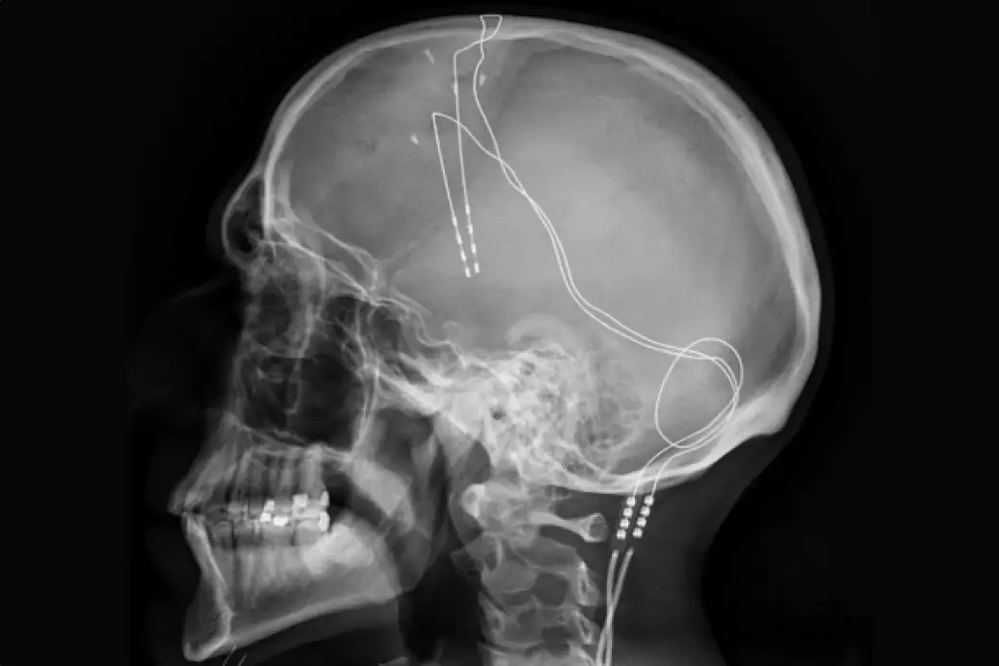

Esta terapia consiste en un procedimiento quirúrgico mediante el cual se colocan implantes cerebrales conocidos como neuroestimuladores. Empleando impulsos eléctricos a través de los electrodos implantados en zonas concretas del cerebro, estos implantes tratan trastornos del movimiento, temblores o afectaciones como las antes mencionadas. En otras palabras, cambia la actividad cerebral de manera controlada.

Fuente: Wikipedia

Por su complejidad, no está pensada para todo el mundo, ya que se trata de una intervención compleja y no exenta de riesgos y, posteriormente, efectos secundarios. Los implantes cerebrales constan de unos finos cables con electrodos, anclajes para evitar que se muevan y el propio neuroestimulador. Todo ello implantado en el cerebro en una o dos intervenciones.